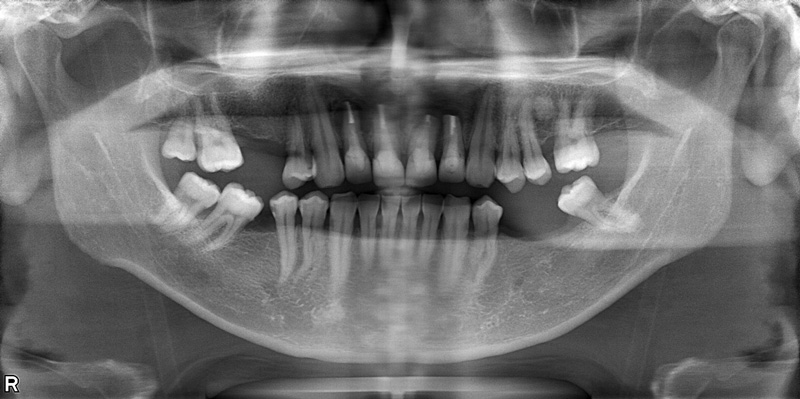

71歳女性

治療前

| 施術名 | インプラント治療 インプラントオーバーデンチャー治療 |

| 施術の説明 | インプラント治療とは、歯を抜いた所にチタン製の人工歯根を埋入し、新しく歯を入れる方法です。上顎は、入れ歯の支えとしてインプラントを使用しています。 |

| 施術の副作用 (リスク) | 腫れや疼痛を感じる、違和感を感じるなどの症状を生じることがあります。 |

| 施術の価格 | 120万円~+消費税 |